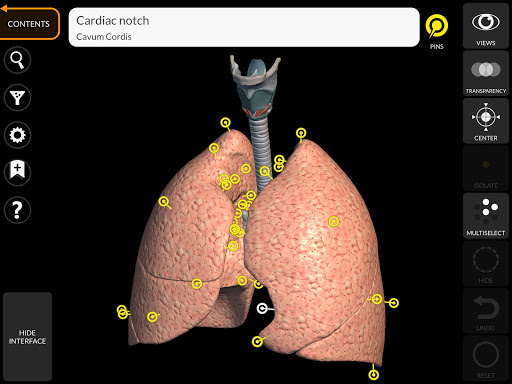

"Anatomy 3D Atlas" vous permet d'étudier l'anatomie humaine de manière simple et interactive.

Grâce à une interface simple et intuitive, il est possible d'observer chaque structure anatomique sous n'importe quel angle.

Les modèles anatomiques 3D sont particulièrement détaillés et avec des textures jusqu'à une résolution de 4k.

La subdivision par régions et les vues prédéfinies facilitent l'observation et l'étude de parties individuelles ou de groupes de systèmes et les relations entre différents organes.

• Système respiratoire